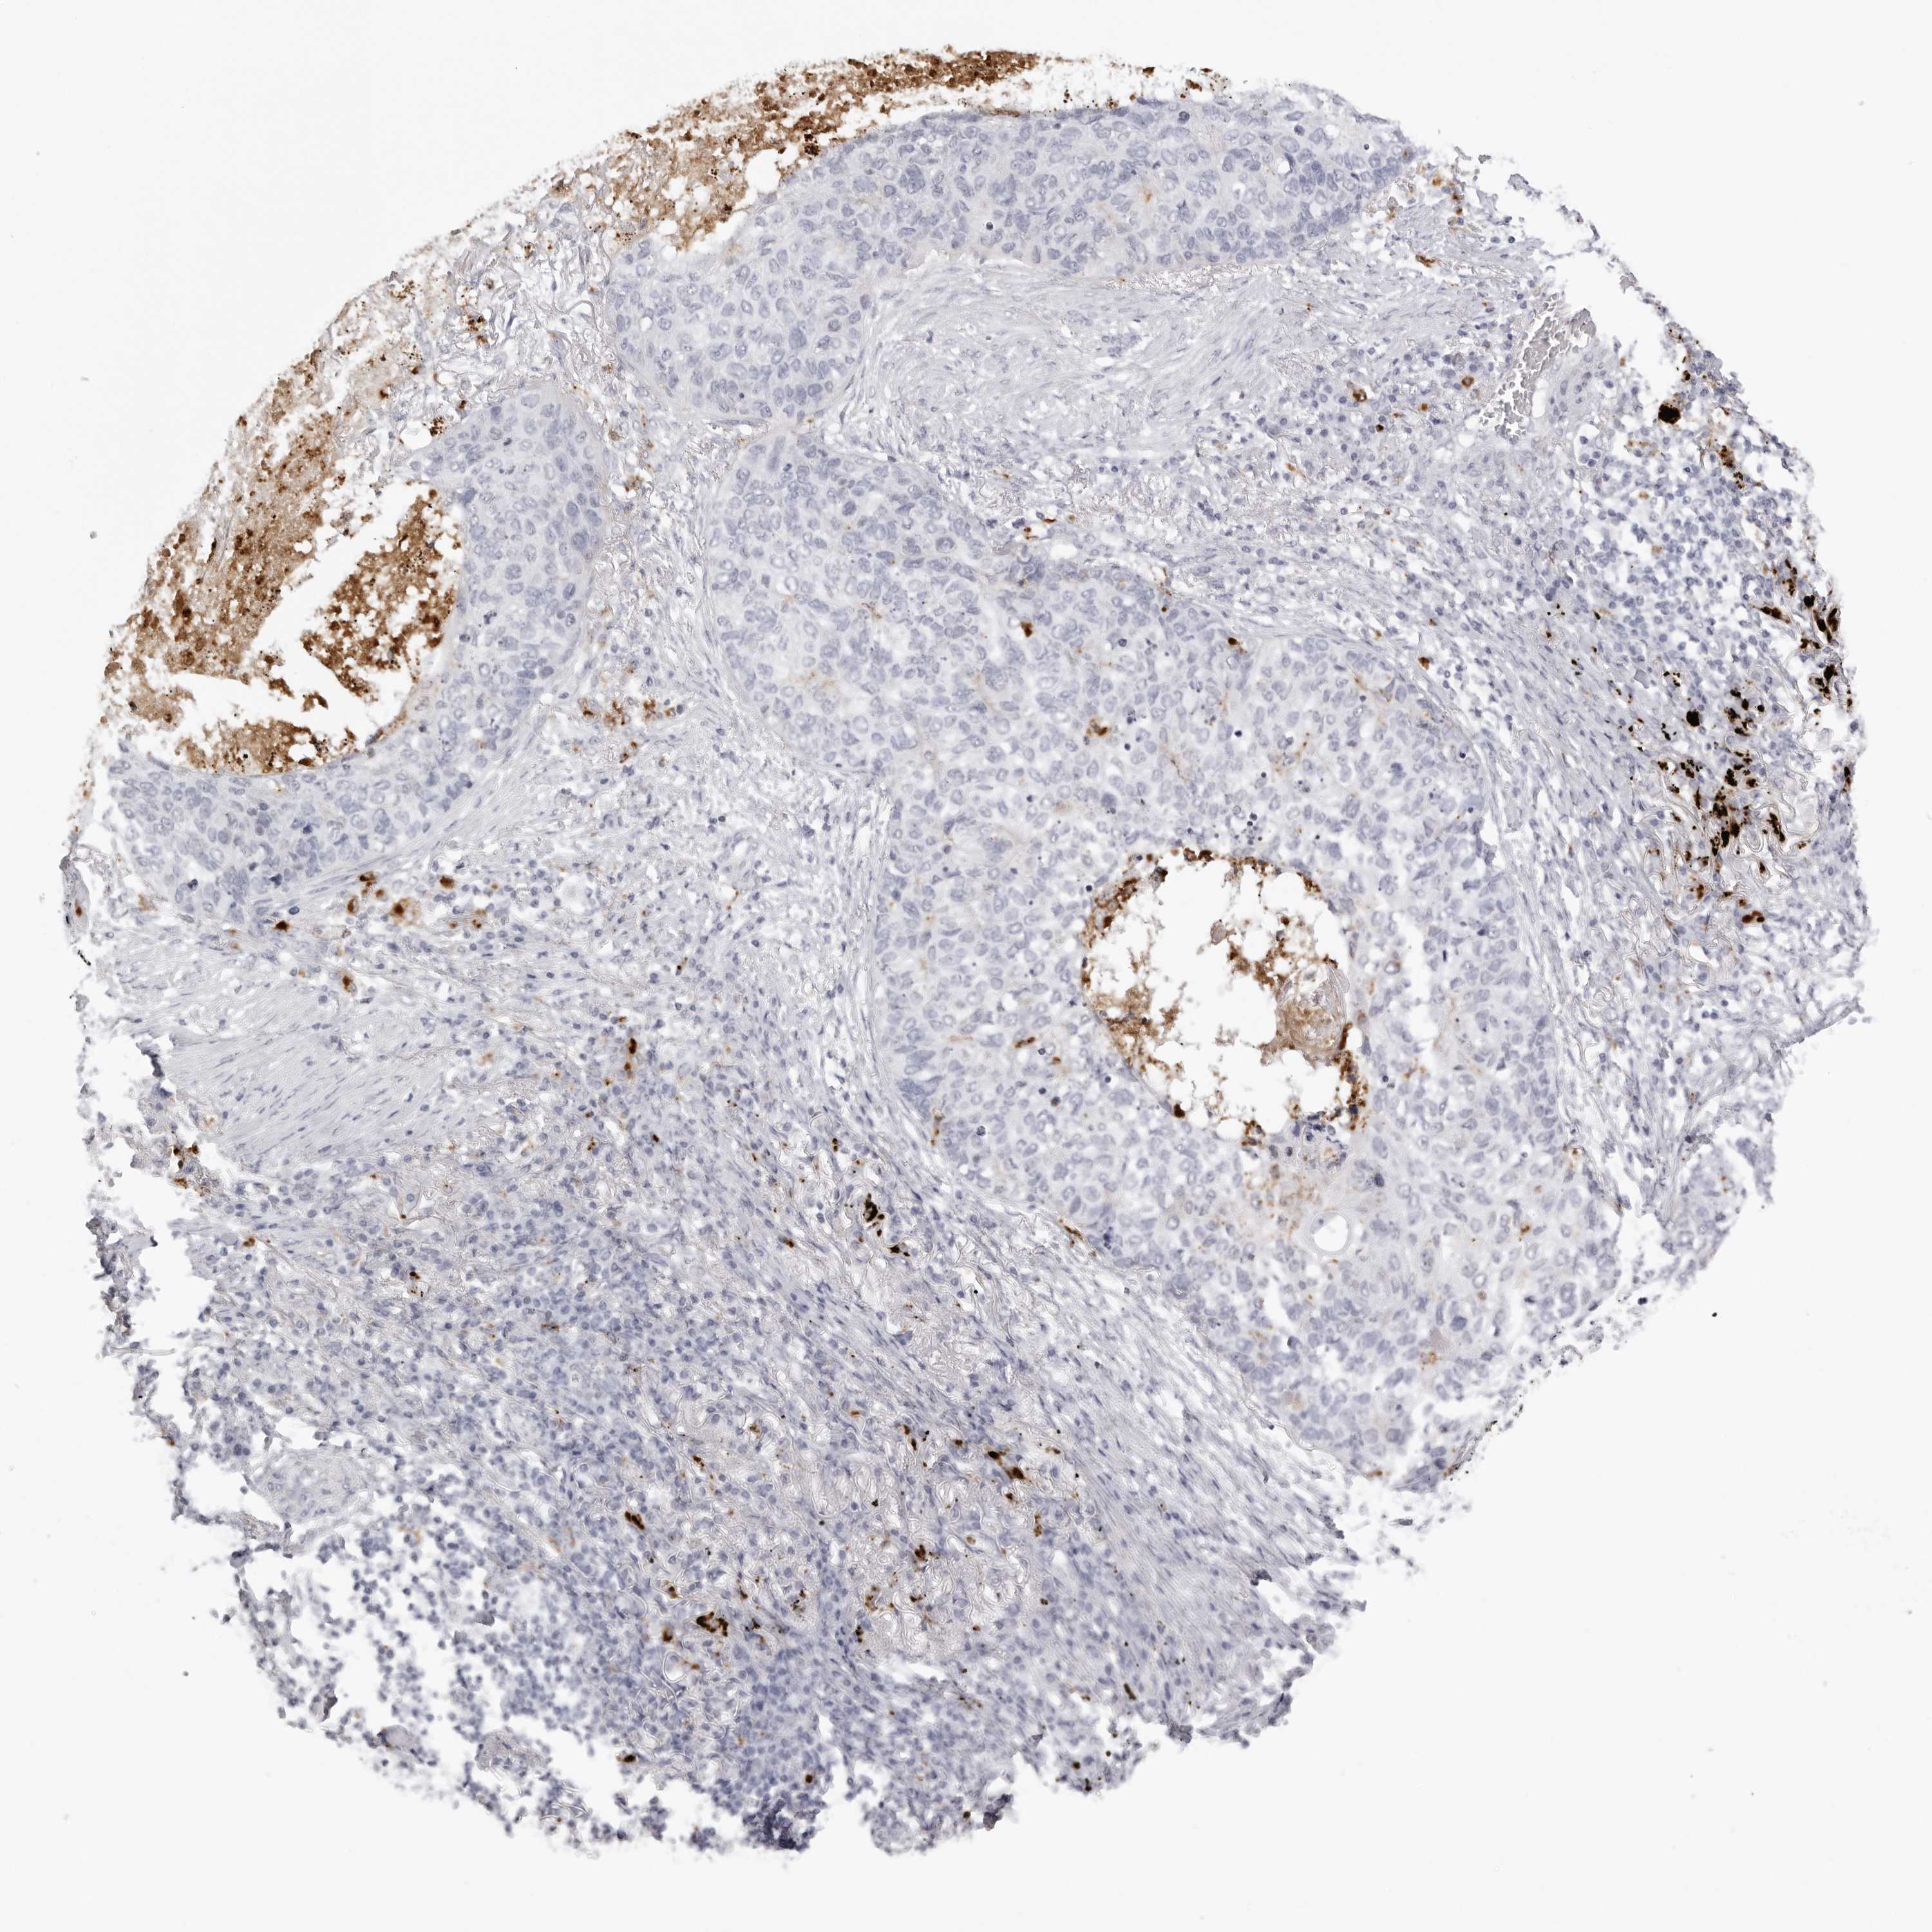

LUNG SQUAMOUS CELL CARCINOMA (TCGA) - Interactive survival scatter ploti

The Survival Scatter plot shows the clinical status (i.e. dead or alive) for all individuals in the patient cohort, based on the same data that underlies the corresponding Kaplan-Meier plots. Patients that are alive at last time for follow-up are shown in blue and patients who have died during the study are shown in red.

The x-axis shows the expression levels (FPKM) of the investigated gene in the tumor tissue at the time of diagnosis. The y-axis shows the follow-up time after diagnosis (years). Both axes are complimented with kernel density curves demonstrating the data density over the axes. The top density plot shows the expression levels (FPKM) distribution among dead (red) and alive patients (blue). The right density plot shows the data density of the survived years of dead patients with high and low expression levels respectively, stratified using the cutoff indicated by the vertical dashed line through the Survival Scatter plot. This cutoff is automatically defined based on the FPKM cutoff that minimizes the p-score. The cutoff can be changed by dragging the vertical line or by entering a cutoff value in the square labeled "Current cut-off".

Under the Survival Scatter plot the p-score landscape (black curve; left axis) is shown together with dead median separation (red curve; right axis). Dead median separation is the difference in median mRNA expression between patients who have died with high and low expression, respectively. It is calculated as follows: median FPKM expression of dead patients with high expression - median FPKM expression of dead patients with low expression. This is intended to aid the user in visually exploring custom cutoffs and the associated p-scores and dead median separation.

Individual patient data is displayed and can be filtered by clicking on one or more of the category buttons on the top of the page. Categories describing expression level and patient information include: high, low, alive, dead, female, male and tumor stages. The scale of the x-axis can be toggled between linear and log-scale by clicking on the "x log" button. Mouse-over function shows TCGA ID, patient information and mRNA expression (FPKM) for each patient.

& Survival analysisi

Kaplan-Meier plots summarize results from analysis of correlation between mRNA expression level and patient survival. Patients were divided based on level of expression into one of the two groups "low" (under cut off) or "high" (over cut off). X-axis shows time for survival (years) and y-axis shows the probability of survival, where 1.0 corresponds to 100 percent.

IL25 is not prognostic in Lung Squamous Cell Carcinoma (TCGA)

TCGA RNA samplesi

RNA-seq data is reported as average FPKM (number Fragments Per Kilobase of exon per Million reads), generated by the The Cancer Genome Atlas (TCGA) .

Normal distribution across the dataset is visualized with box plots, shown as median and 25th and 75th percentiles. Points are displayed as outliers if they are above or below 1.5 times the interquartile range. FPKM values of the individual samples are presented next to the box plot.

Average pTPM 0.0

Number of samples 489